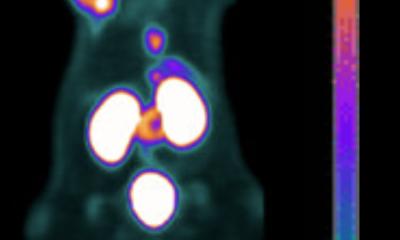

PET scanners are not the only way to image radiotracers. Recent work developed around a phenomenon called Cerenkov luminescence aims to bring a new modality out of preclinical development and into clinical practice.

In conventional optical imaging a light is projected onto the area of study to excite an injected fluorochrome. The more external light, the stronger the obtained signal – but also the scatter and reflectance of the external excitation light, degrading the sought after signal. With Cerenkov luminescence imaging the light emanates from the radiotracer within the body. It is an ultra low signal that requires total darkness and very sensitive cameras to be detected.

Another advantage of Cerenkov luminescence imaging is the cost of the camera, which is 25% of the cost of a PET scanner. Additionally, in pre-clinical animal studies, where usually one mouse can be imaged at a time with PET, Grimm pointed out, ‘we can image five mice at the same time and it takes about five minutes.’ The ability to capture Cerenkov luminescence remains the great challenge. Going inside the patient during endoscopic procedures shows promise because the human body serves as a natural shield for the faint blue light.